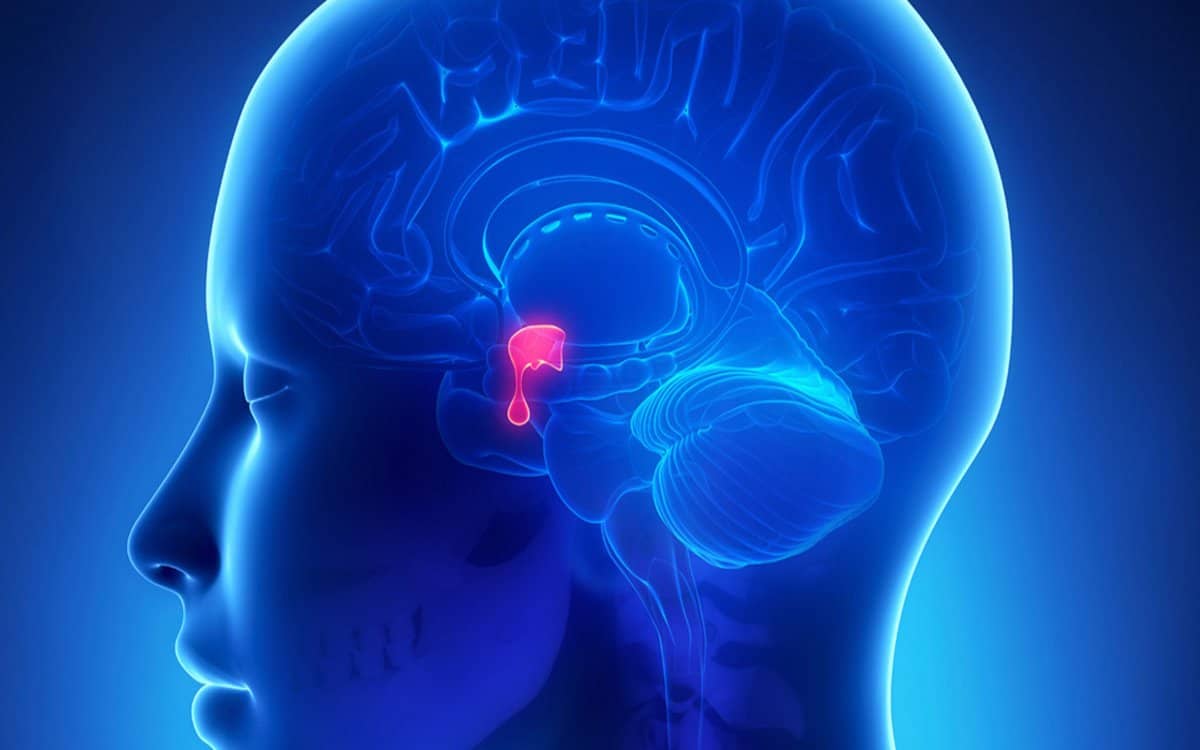

يتعرض الكثير من الأشخاص إلى الإصابة بالأورام التي تستهدف الغدة النخامية، وفي الغالب تكون هي أورام حميدة، وغير خبيثة، تستهدف تلك الغدة، التي تقع في منطقة قاعدة الدماغ، ويكون مكانها خلف الأنف مباشرة، ولا يزيد حجمها عن حجم حبة البازلاء، وتحت عنوان تجربتي مع ورم الغدة النخامية، خاض الكثيرون تجارب واتبعوا طرق لعلاج الغدة والأورام بداية من من استعمال العقاقير والأدوية، التي تستطيع التحكم في نمو الورم وتطوره، وآخرون خاضوا عملية استئصال الورم ذاته.

في البداية يجب التعريف بورم الغدة النخامية، بأنه عبارة عن خلايا تنطور بشكل وطريقة شاذة في الغدة النخامية، وتعمل عدد من أورام الغدة النخامية إلى إفراز الهرمونات بإفراط، وخاصة تلك التي تنظم مهام جسد الإنسان الضرورية، كما ينتج عن بعض أورام الغدة النخامية مستويات أضعف من هرمونات الغدة النخامية.

- من أكثر المضاعفات شيوعًا لورم الغدة النخامية هي فقدان الرؤية، حيث أن تلك الغدة تقع في مكان تقابل عصبي العينين، ومع ضغط الورم على أعصاب الرؤية، يحدث خلل في وظيفتها.

- ومن مضاعفات ورم الغدة النخامية هي حدوث نقص بصورة دائمة في الهرمونات.